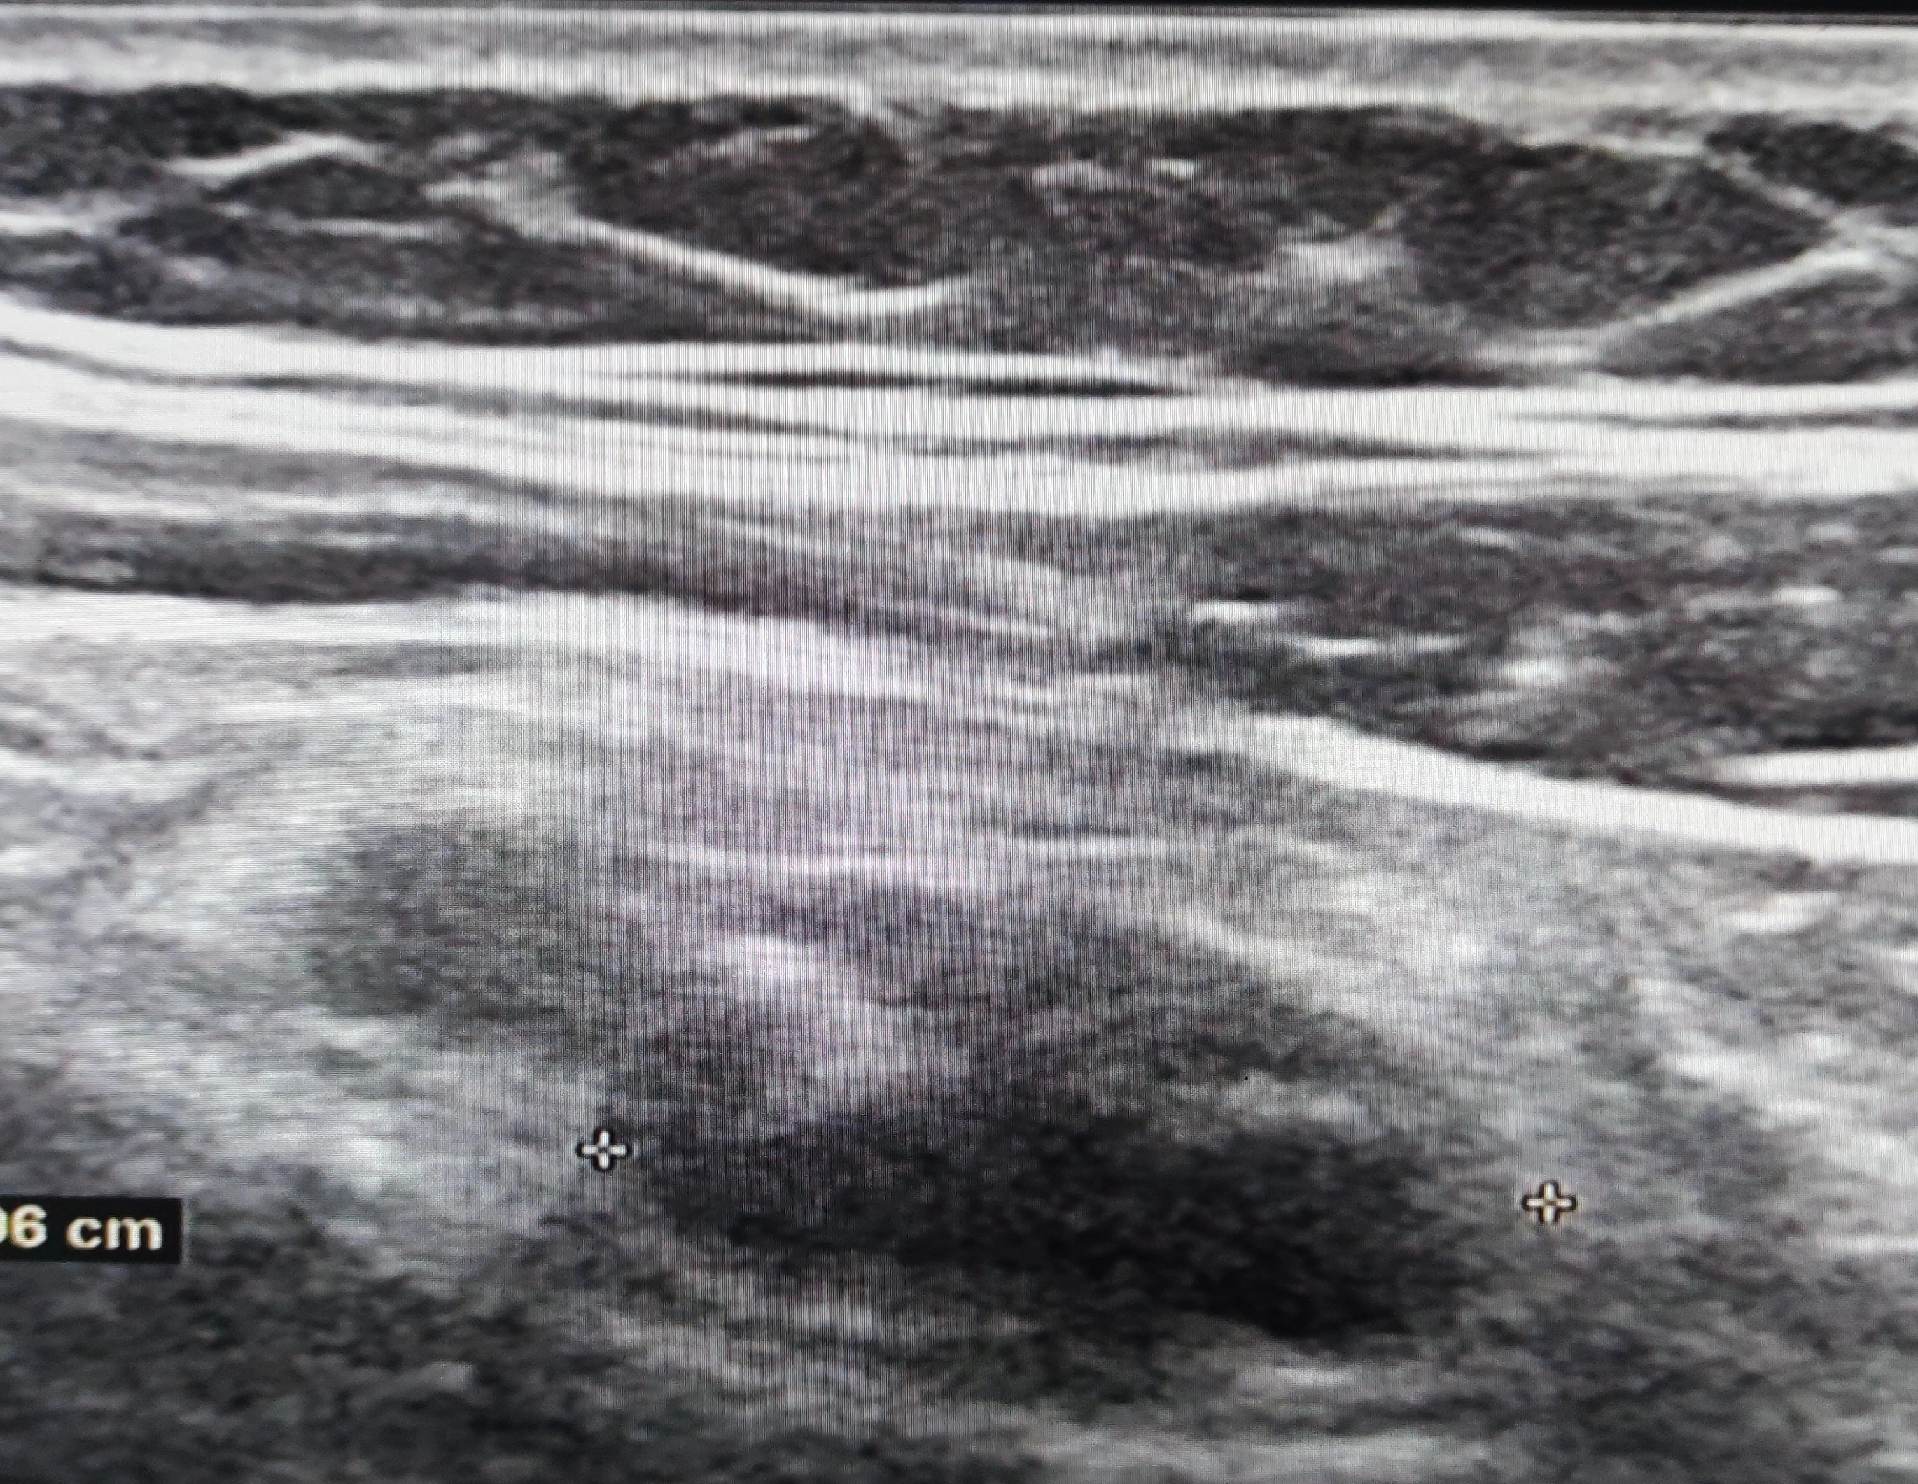

阑尾肿大。阑尾炎性改变 后位阑尾 盲端较难显示 与CT对照 随访化脓性阑尾炎已手术